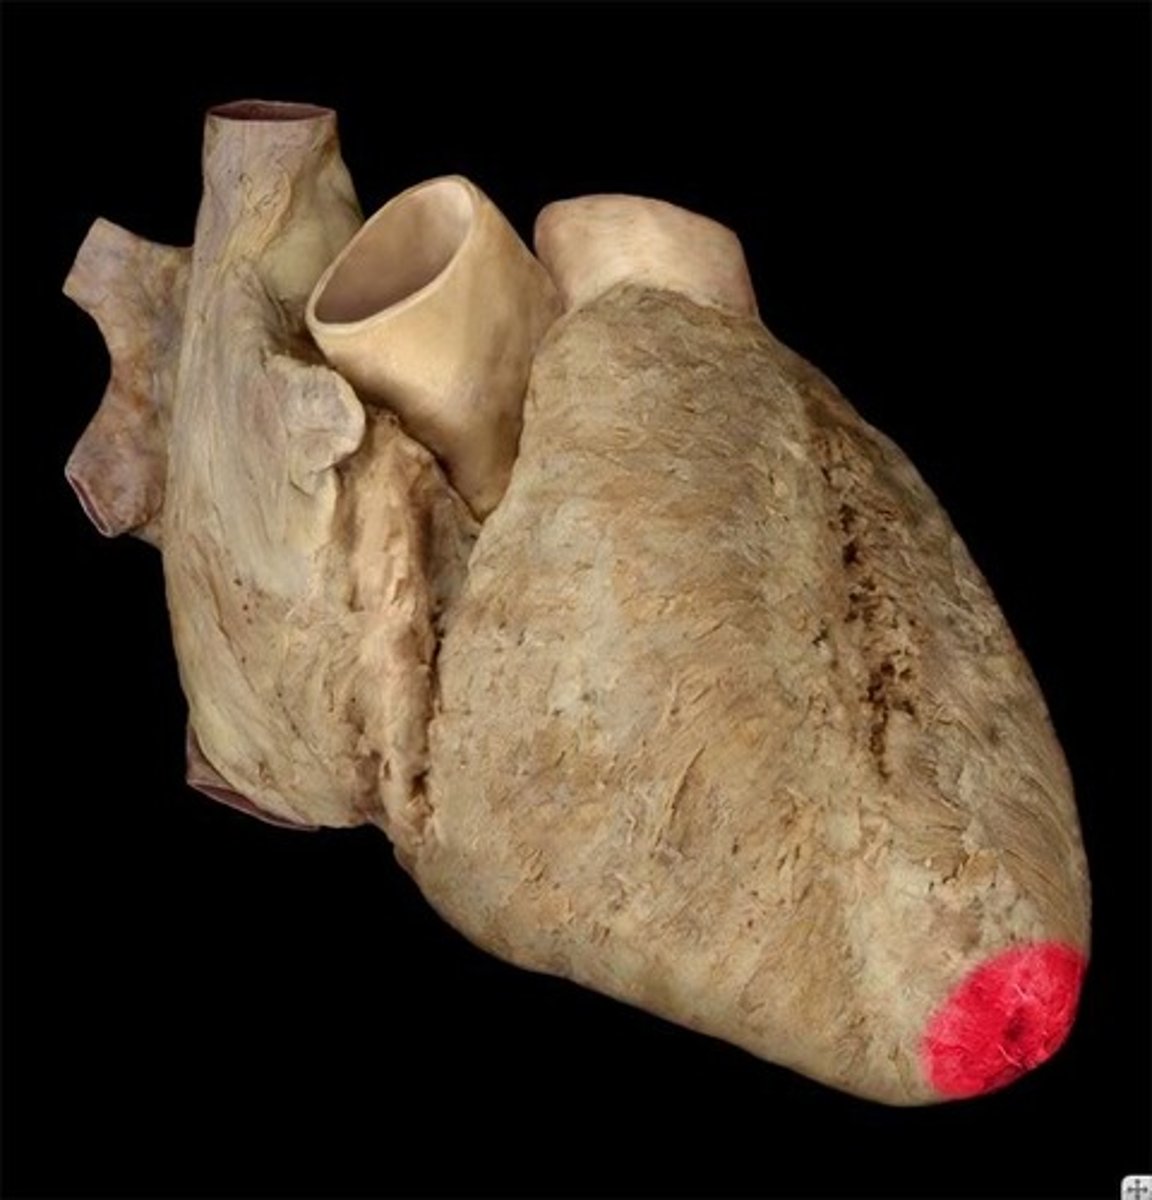

Apex of the heart

lower tip of the heart (feature)

great cardiac vein

begins in the anterior interventricular sulcus

left side of the 'T'